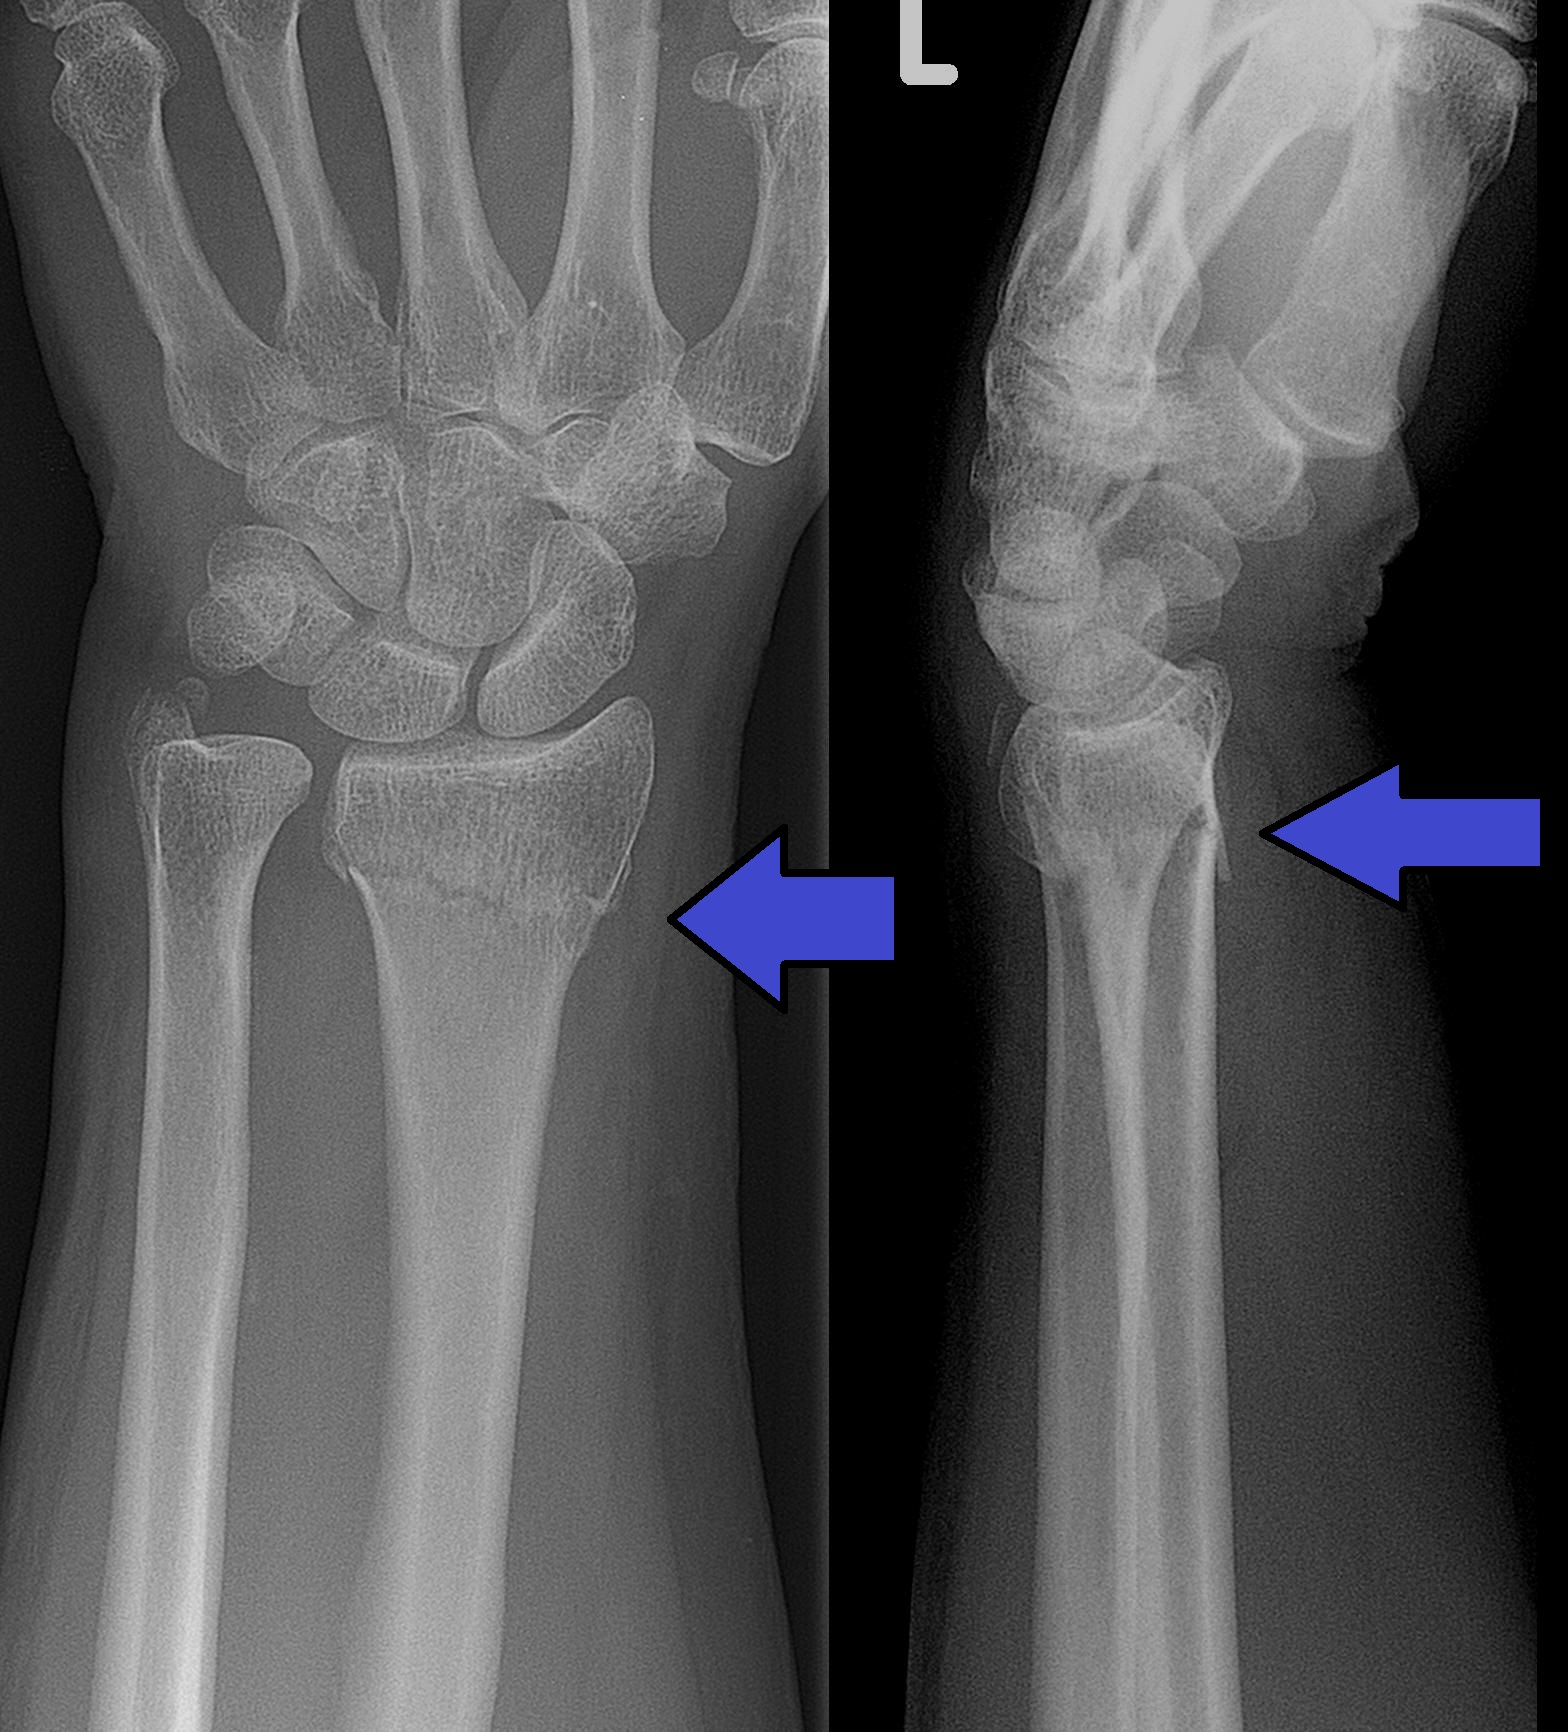

- 骨折检测:在某些部位(如腕骨)准确率超过人类医生

腕部Colles骨折(桡骨远端骨折)X射线图像,这是最常见的腕部骨折类型之一

- COVID-19筛查:快速识别肺部感染特征

- 腕部骨折X射线:Wikimedia Commons - Collesfracture,CC BY-SA 3.0